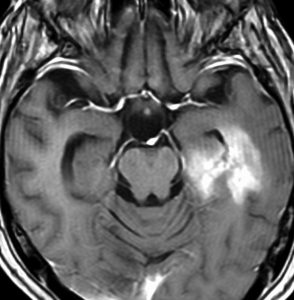

30代の患者さんです。起立性低血圧や呼吸苦,右片麻痺と多彩な脳神経症状で発症しました。

左はT2強調画像で,延髄を中心とするびまん性グリオーマの所見です。右はがドリニウム増強像で,一部が増強されて白く見えています。

50.6Gy/28fr, TMZ 24コースの治療をした4年後のMRIです。腫瘍は縮小して固まったようにみえ,症状も落ち着いて自宅で暮らせてました。

しかしこの後に,激しい腫瘍再燃があり制御できませんでした。

脳幹部に発生するAAを,画像だけで「びまん性正中グリオーマ diffuse midline glioma」 と区別することは難しいです。だとすれば生検手術が必要か ? といえばそうとも言えません。どちらであっても治療方法は同じだからです。ただし,平均的な生命予後が退形成性星細胞腫の方が長く,治る患者さんもいます。